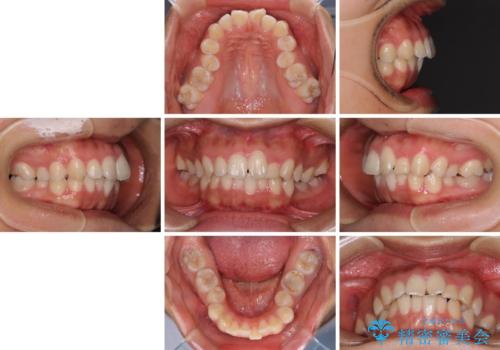

- 咬み合わせと口元の突出感を気にして来院された患者様です。

上顎に対して、下顎が後方にある咬み合わせであるため、上顎左右小臼歯のみの抜歯か、下顎左右小臼歯も抜歯とするのか悩むところでした。

まずは上顎のみ抜歯を行って矯正治療を進め、下顎小臼歯も抜歯が必要となれば速やかに抜歯することとしました。

上顎抜歯のみでは奥歯の咬み合わせを改善することが困難であったため、途中で下顎小臼歯も抜歯をしました。

抜歯のタイミングが遅れると治療期間が長期化するため、速やかに抜歯の判断をし、2年強の期間で治療を終えることができました。